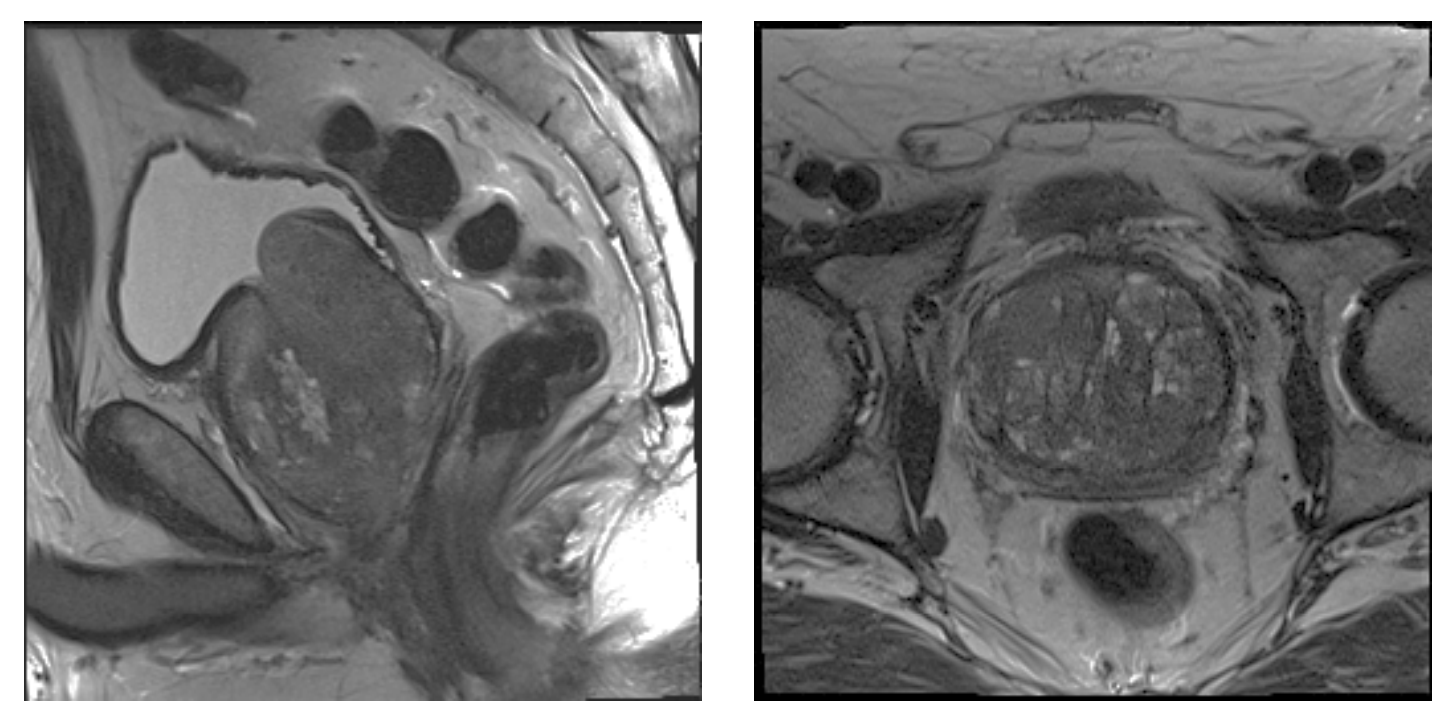

A 74-year-old male with past medical history of hypertension, coronary artery disease, and BPH with LUTS refractory to medical management presented for evaluation. The patient underwent an MRI of the prostate demonstrating a 182 cc gland with an enlarged transitional zone measuring 144 cc (Figure 1). The patient’s baseline IPSS and QoL were 18 and 5, respectively. Given the patient’s prostate gland size, and medical comorbidities, he elected to undergo PAE for management of his LUTS. On the day of his PAE, right common femoral arterial access was obtained and a pigtail DSA was obtained delineating pelvic arterial anatomy. On the right, the prostatic artery arose from a vesiculoprostatic trunk, with a shared origin with the superior vesicular artery (Figure 2). This was selectively catheterized with a progreat alpha microcatheter (Terumo, Tokyo, Japan), and 016” fathom microwire (Boston Scientific, Marlborough, MA). Angiography demonstrated perfusion of the entire right portion of the gland, without evidence of extra-prostatic supply (Figure 3). Embolization was performed with 300-500 micron Embospheres (Merit Medical, South Jordan, UT) to stasis. On the left, the prostatic artery arose from the left obturator artery (Figure 4). This was subsequently catheterized with the same catheter/wire combination, with angiography demonstrating left glandular perfusion without extra-prostatic supply (Figure 5). Embolization was again performed to stasis with 300-500 micron Embospheres. The patient did well post-procedurally with self-limited urinary frequency and dysuria for 3 days. By 3 months post PAE, the patient reported a significant improvement in his LUTS, with an IPSS/QoL of 3 and 0, respectively.

The patient had a long-term response to PAE for approximately 5 years, at which point he experienced gradual recurrence of his LUTS. He re-presented with an IPSS/QoL of 27/5, respectively. At this point, repeat MRI of the prostate was obtained demonstrating a total gland volume of 119 cc, with a transitional zone volume of 94 cc (Figure 6). Given his recurrence of symptoms, and enlarged gland not amenable to standard surgical therapies, he elected to undergo repeat PAE.